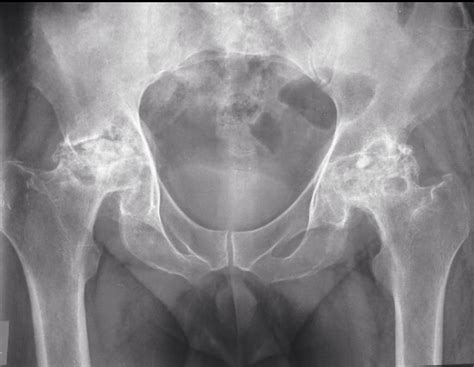

Since the condition often starts invisibly, physicians use advanced imaging to confirm the presence of bone death. X-rays are typically the first line of defense, though they often fail to show early-stage damage. An MRI scan is widely considered the gold standard for diagnosing avascular necrosis, as it can detect changes in the bone marrow before the structure of the bone actually changes.

In addition to imaging, doctors may ask about your medical history, specifically regarding steroid use or prior injuries. Understanding your lifestyle, occupation, and family health history is also essential for a comprehensive evaluation.